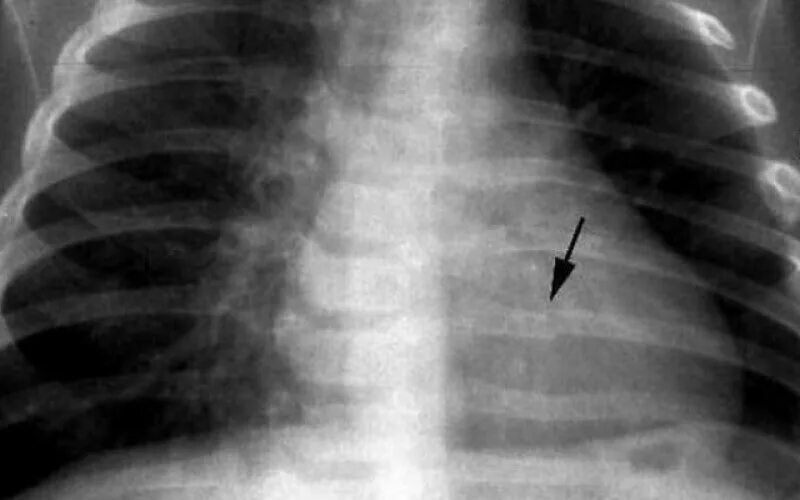

Множественные ребра